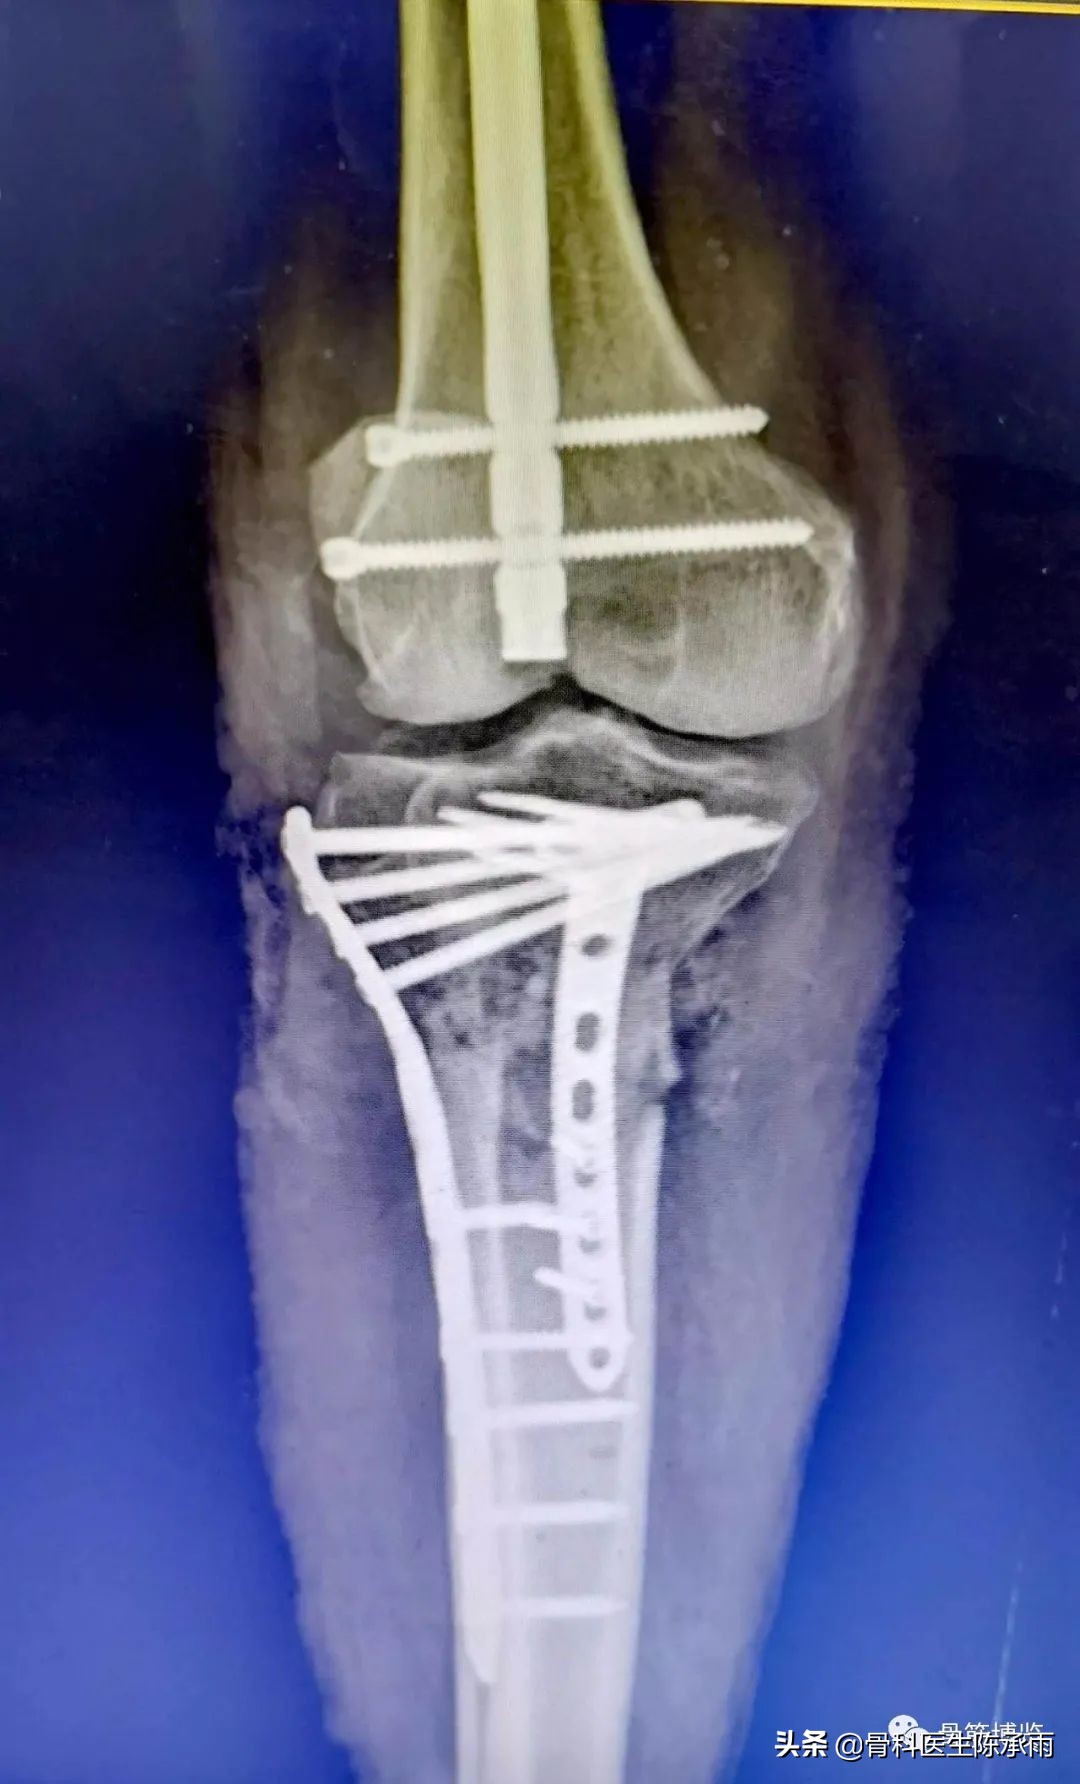

这2例患者皮肤条件差,全身多发骨折,小腿皮肤条件差,1例筋膜高压切开,1例整个小腿布满张力性水泡,胫骨骨折都在伤后30天才能手术。

下例胫平台骨折皮肤条件差,内侧板取两端小切口置入内板固定。胫骨结节处撕脱骨折以1枚拉力螺钉固定。